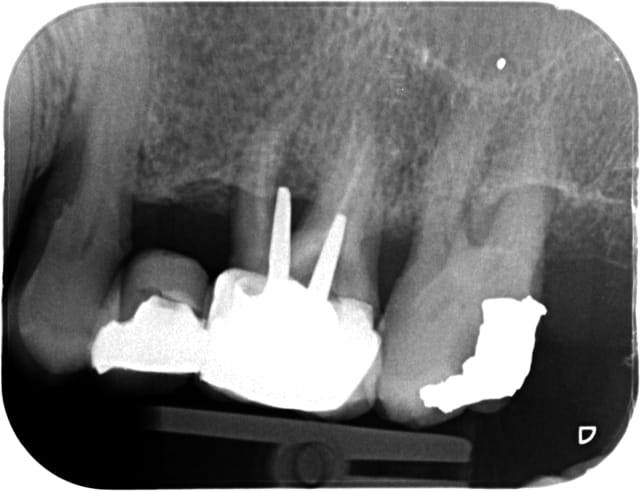

Moi je me dis, je suis surement pas le meilleur dentiste... mais ça va. En fin de semaine, je regarde les travaux que j'ai faits, avec un peu de recul et sereinement, comme une sorte de "contrôle qualité interne", avec un esprit objectif (comme si c'était un autre dentiste qui avait réalisé le soin).

Le pbm des rempla/collab courtes c'est que t'as pas de vision sur le moyen/long terme de ton travail.

Mais si comme moi tu as soigné ta famille, regarde comment vieillissent tes soins et tu verras que la qualité est là.

Il faut être fier de toi et de ce que tu fais !

Sinon faut pas s'en faire... lui (ou elle), il s'en est fait moins que toi (cf radio jointe) !!